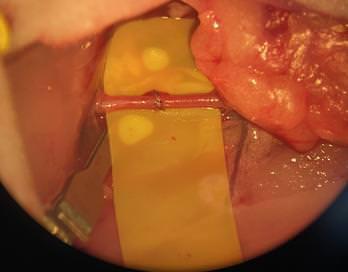

Jig-guided hip revisions

For the first time, Gomina has developed an extraction set that allows a hip revision to be done with minimal bone loss. Thanks to innovative production technologies, it is possible to manufacture dimensionally rigid chisels with different radii. The precision ground, sharp cutting edges of the chisels are the result of Gomina’s many decades of expertise.

The bespoke crafted jigs manufactured by Gomina ensure the application of a precise separation of bone and prosthesis. This innovative pioneering extraction set from Gomina makes surgeon’s work far easier, leading to shorter operating times. Entirely for the patient’s benefit.